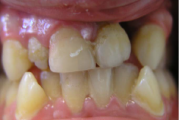

Kaasasündinud hammaste puudumine

Sagedamini puuduvad hambad: teised premolaarid, ülemised lateraalsed intsisiivid, alumised tsentraalsed intsisiivid.

Sümptomid:

vahe esimeste hammaste vahe

(2)

valehambumus

(18)

vahed hammaste vahel

(5)

puuduvad hambad/hammas

(4)